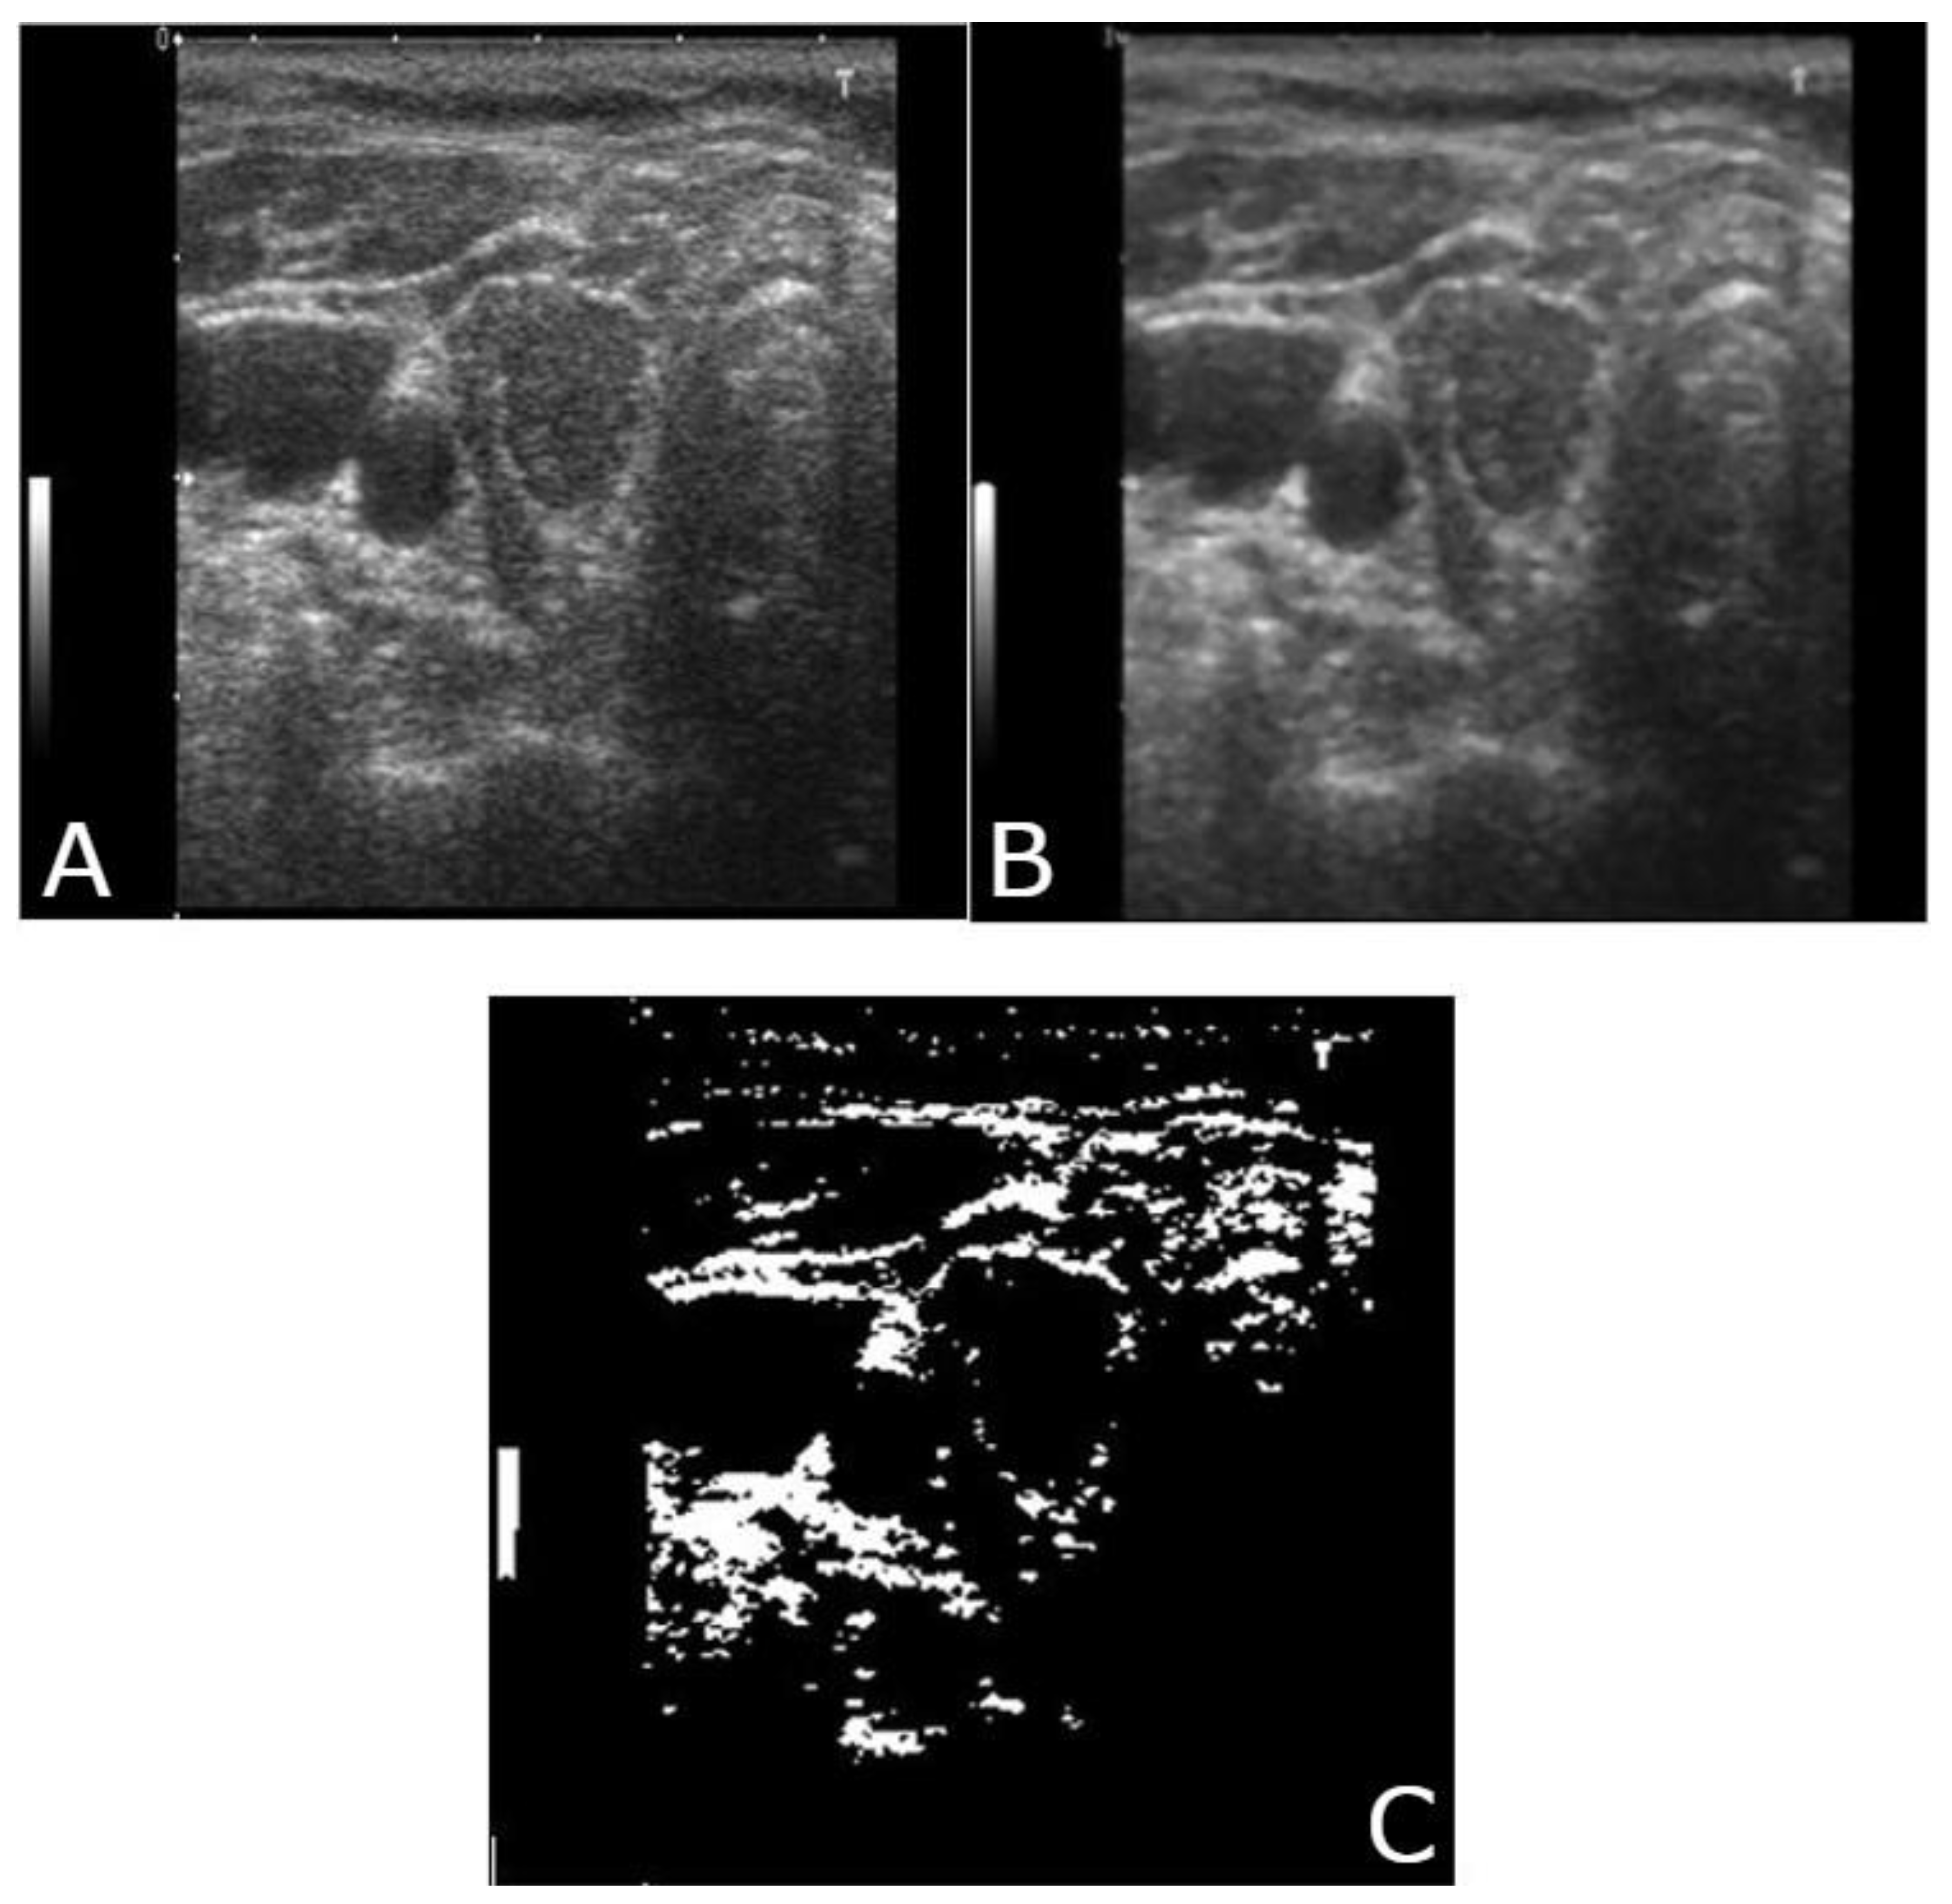

2.5. Segmentation

3.1. Image Analysis and Image Processing